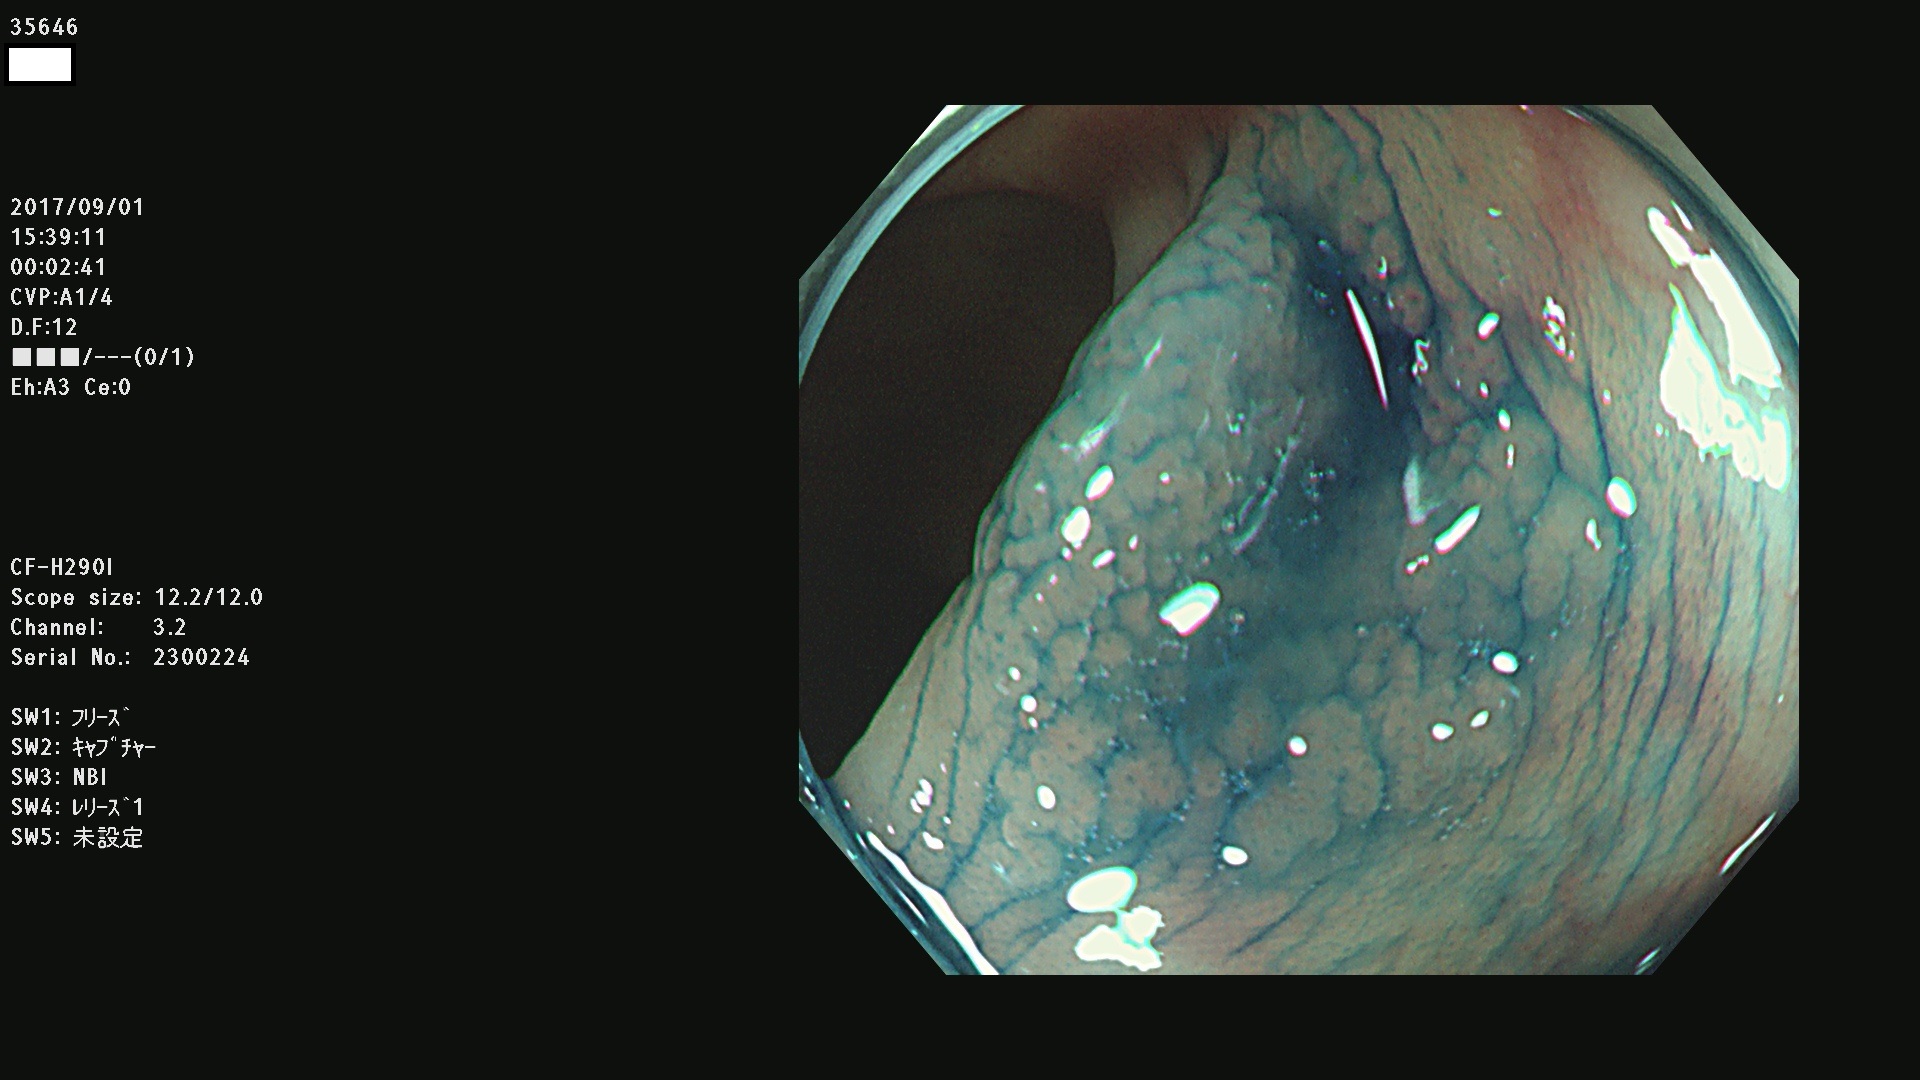

発見困難で危険性の高い平坦型病変(上記100名より抽出)

35600 35603 35604 35609 35612 35613 35614 35619(SSA/Pのみ) 35624 35625 35626 35627 35629 35630 35631 35633 35634 35635 35636 35638 35641 35642 35643 35644 35645 35646(SSA/Pのみ) 35648 35651(SSA/Pのみ) 35652 35653 35655 35656(SSA/Pのみ) 35659 35660 35664 35665 35667 35668 35669 35670 35671 35675 35678 35679 35680 35682 35684 35689(SSA/Pのみ) 35695 35696 35699